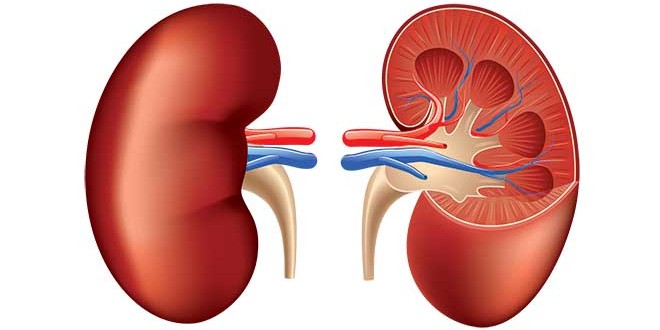

Sofrer com cálculos renais é simplesmente horrível e precisar torcer para conseguir expeli-los é ainda pior. No entanto, um urologista da Universidade Estadual de Michigan, nos Estados Unidos, descobriu uma forma muito peculiar que instiga a eliminação das tão desagradáveis pedras.

Para testar esta teoria, o urologista criou um modelo 3D sintético de um rim com três cálculos renais, que possuíam dimensões menores de 4 milímetros. Então, ele andou na montanha-russa Big Thunder Mountain com a réplica dentro de uma mochila por 20 vezes.